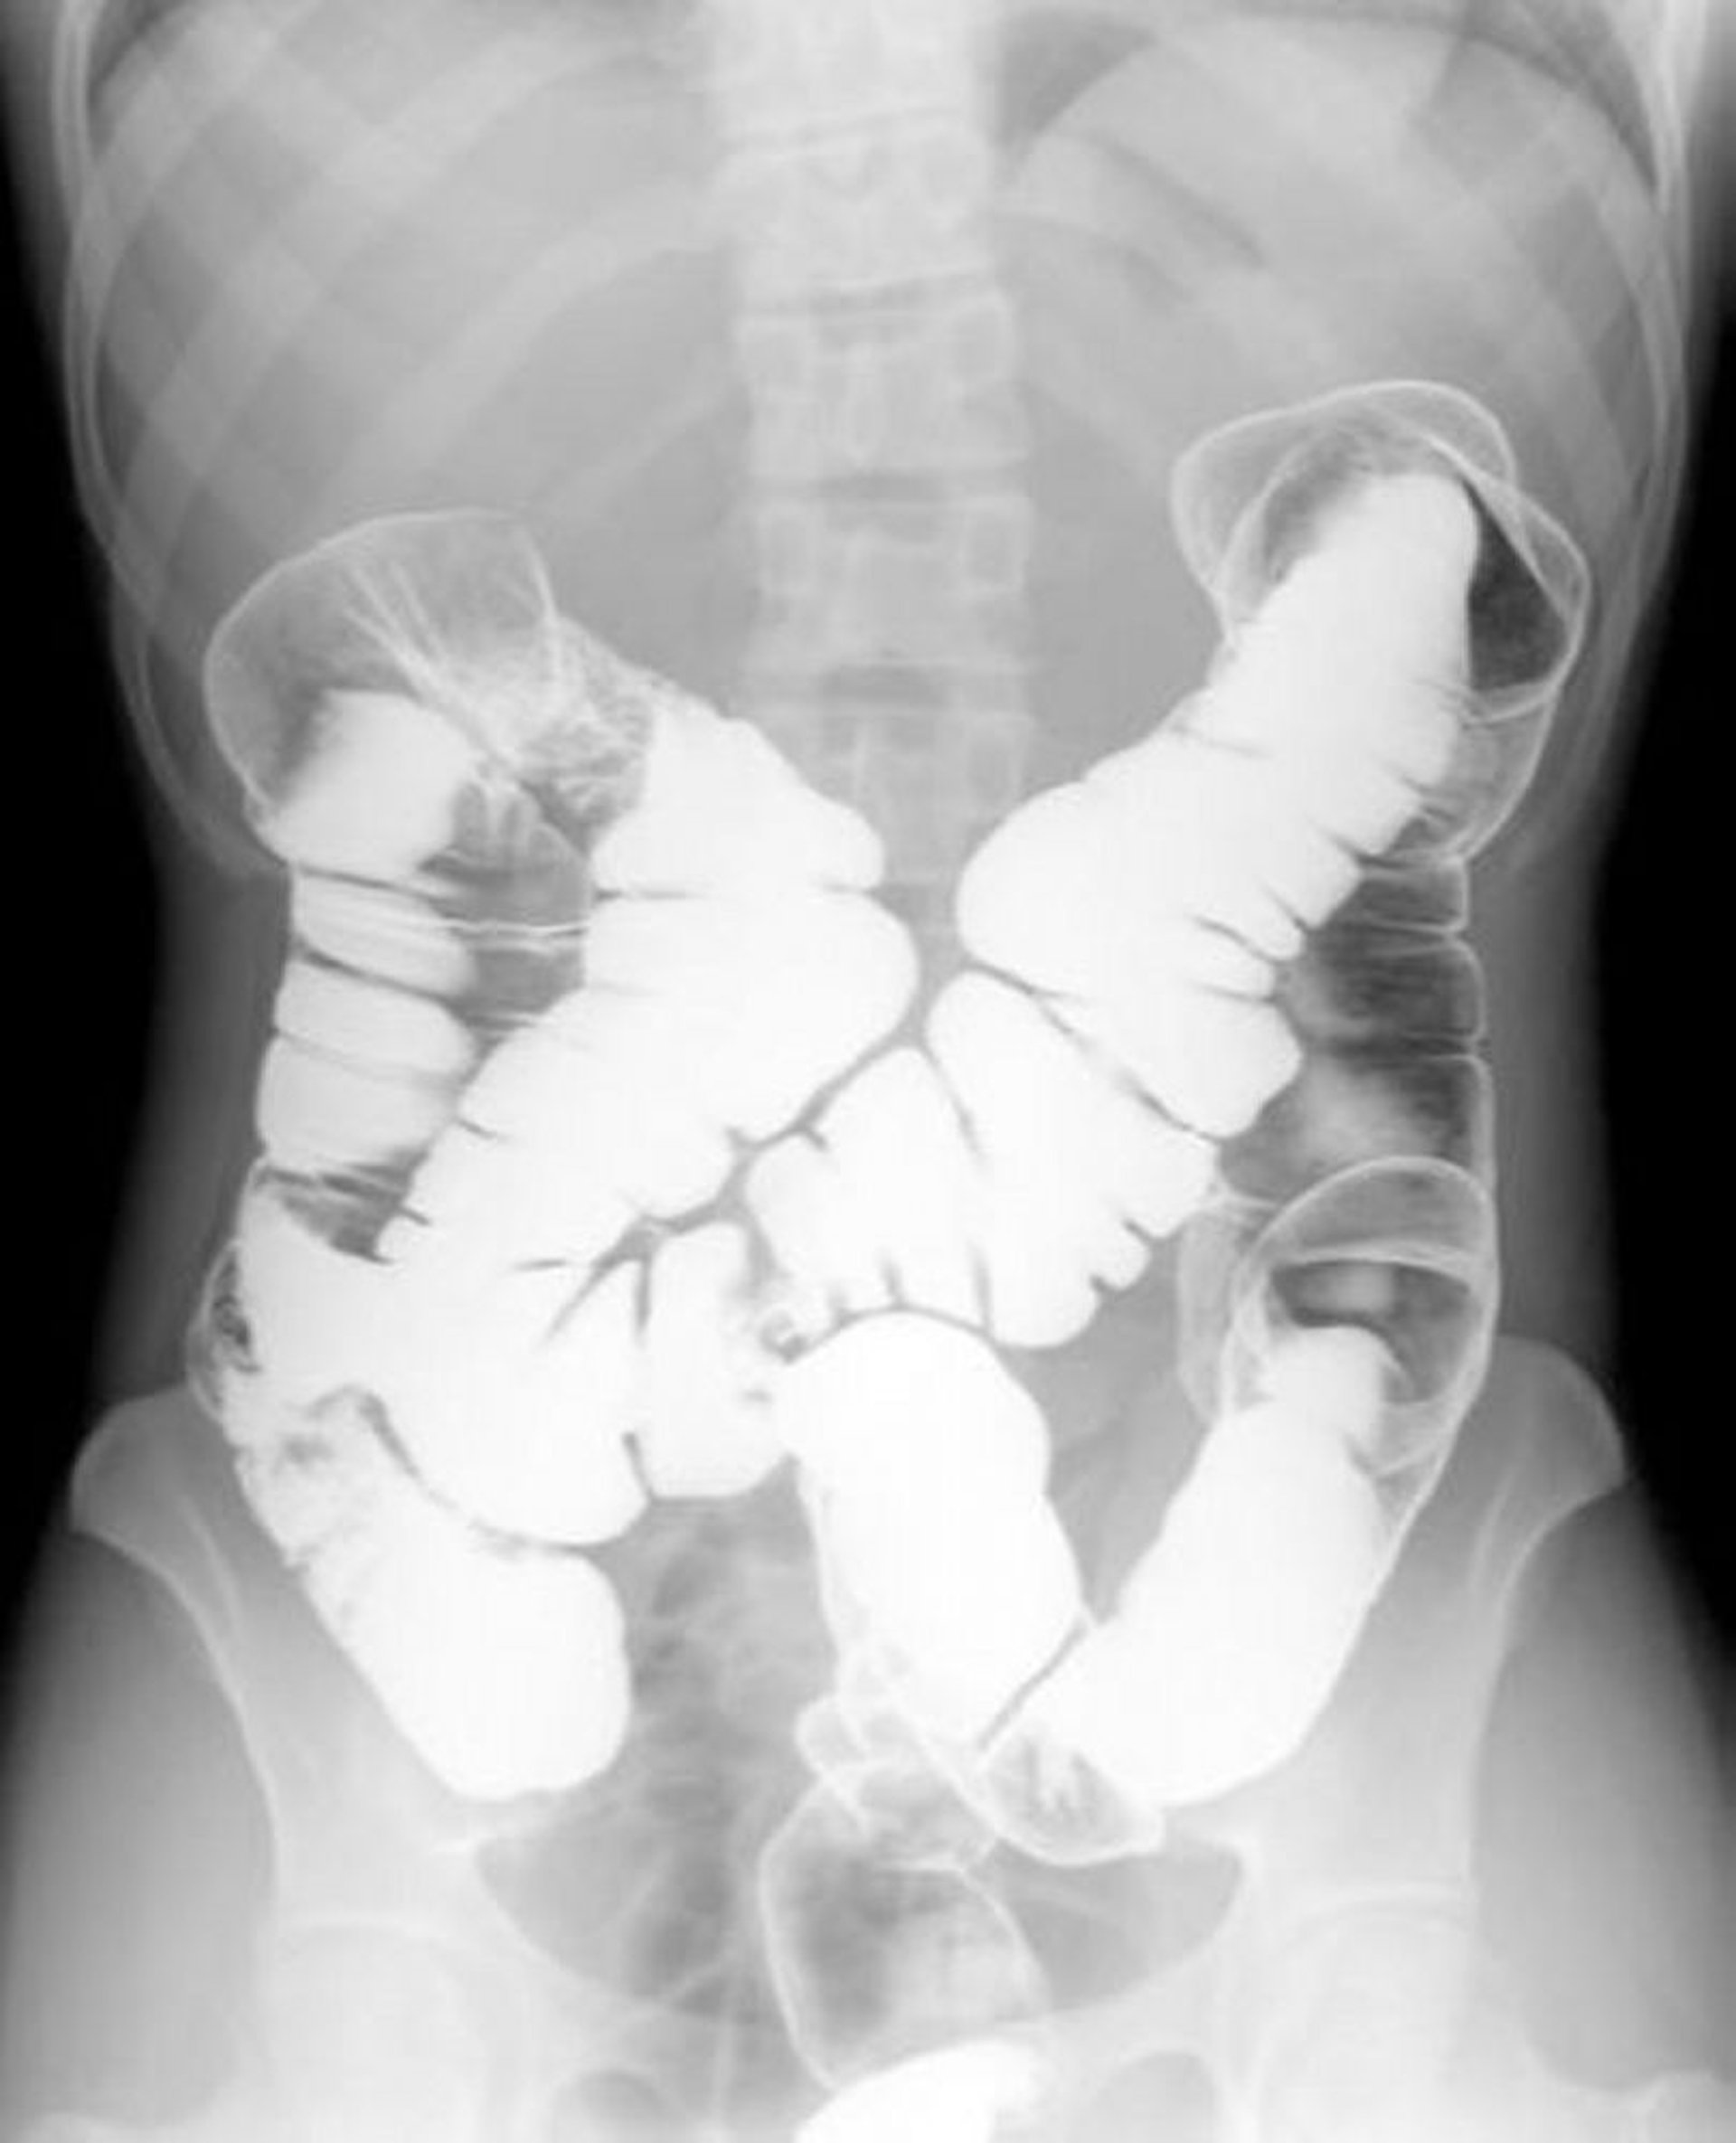

Двоконтрастна іригографія з барієвою клізмою демонструє нормальну анатомічну картину

This image shows the pattern of air and barium within a normal colon.